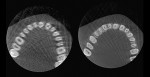

1. Planmeca ProMax 3D Mid CBCT unit with Planmeca CALM technology. 2. A CBCT image without Planmeca CALM (left) and one with Planmeca CALM (right).